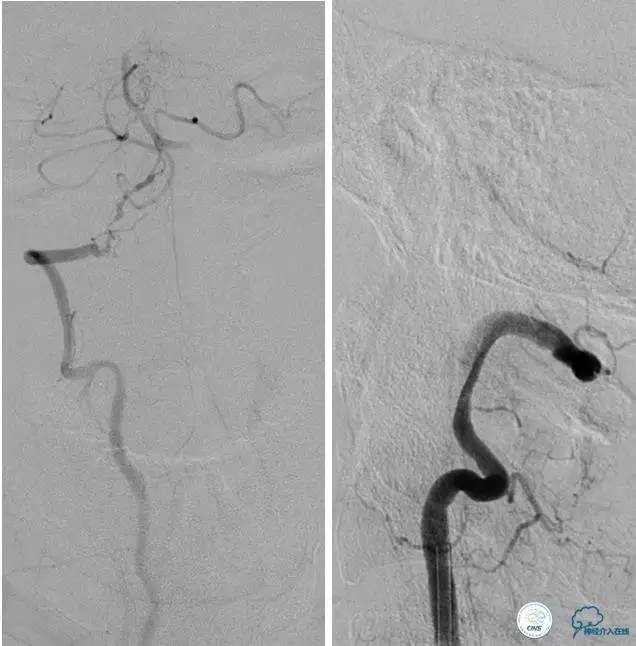

患者:58岁男性,反复头晕,不能站立,视物不清,入院后药物治疗期间再次加重。

▼DSA示右侧椎动脉发育低下,弥漫性狭窄,可以看到左侧椎动脉反流,因此判断左侧椎动脉V4段CTO。

微导丝穿过闭塞段,微导管造影,球扩闭塞段,置入Wingspan支架,血流完全恢复正常。

患者术后2天再次出现卒中发作,药物治疗好转,此后病情稳定。半年后复查DSA,见支架闭塞,侧支循环开放。患者一般情况好,mRS:1分。